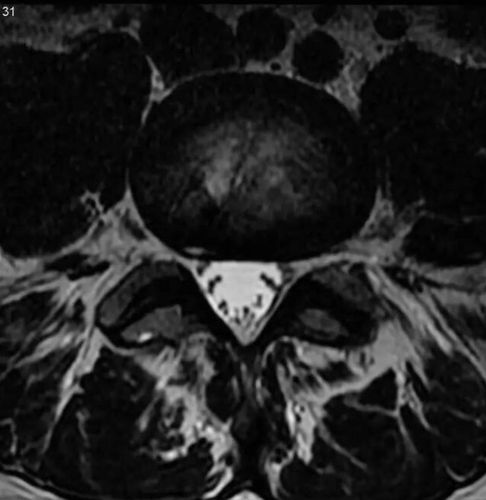

纤维环破裂

纤维环破裂,纤维环撕裂

盘有不同程度的退行性改变后,在外力因素的作用下,椎间盘的纤维环破裂

神经根下方的纤维环破裂口

纤维环撕裂

纤维环破裂图片

腰椎纤维环撕裂

腰椎纤维环破裂